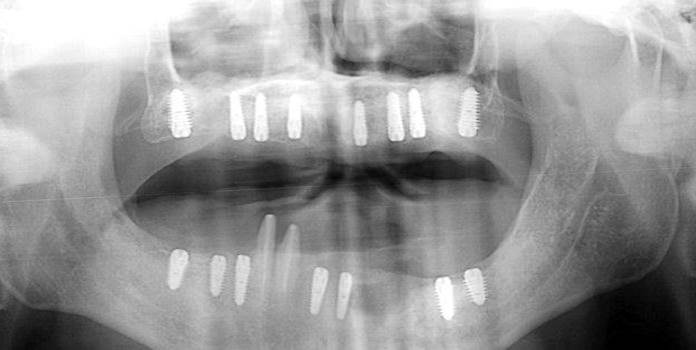

Clinical case: Full-mouth implants for mandibular & maxilla - restored using mixed prostheses

- Courtesy of Dr. Hyun Jun Kim, Korea -